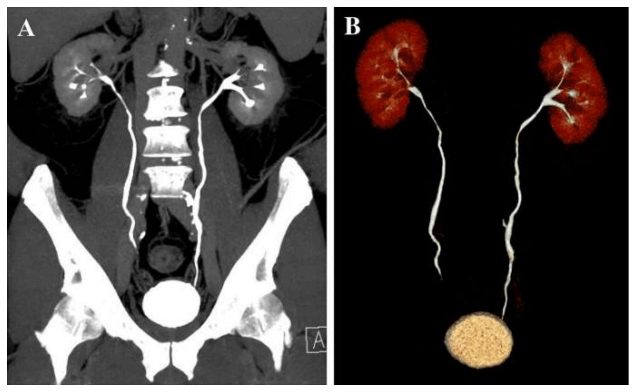

CT Urography

A computerized tomography (CT) urogram is an imaging exam used to evaluate the urinary tract. The urinary tract includes the kidneys, bladder and the tubes (ureters) that carry urine from the kidneys to the bladder